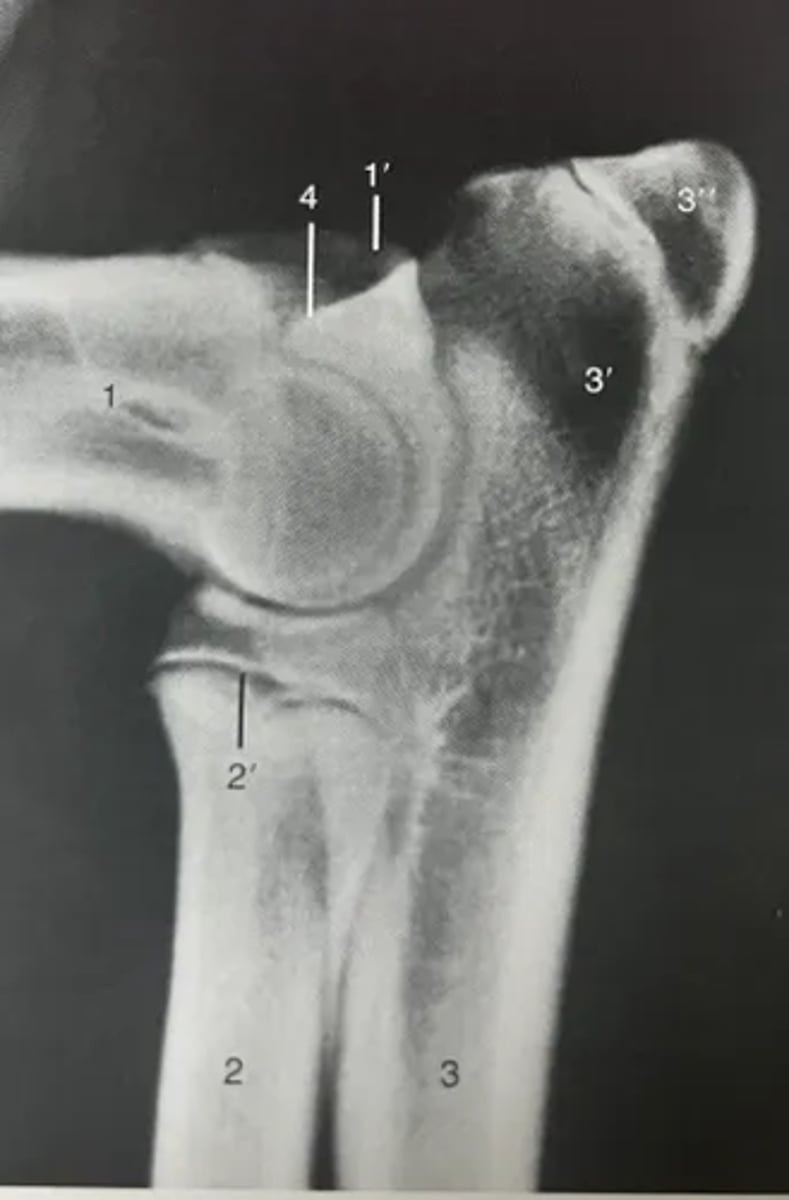

Identify features of the elbow on a radiograph.

1. Humerus

1'. Medial epicondyle

2. Radius

3. Ulna

3'. Olecranon

3''. Apophysis of tuber olecrani

4. Anconeal process